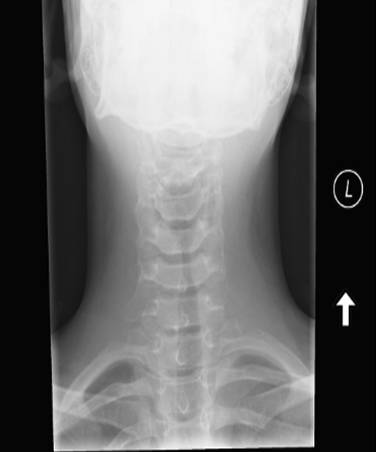

A soft tissue neck x-ray was ordered in the Emergency department.

PLEASE DESCRIBE THE X-RAY?